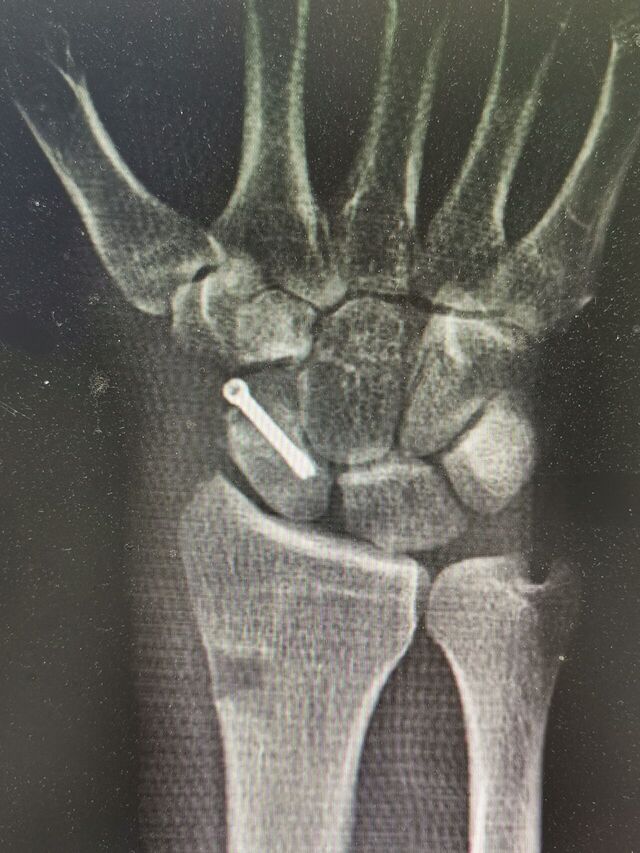

舟骨陈旧骨折,驼背畸形

术中失去对合参照

IMG_20240807_154525.jpg

IMG_20240807_154538.jpg

IMG_20240807_154625.jpg